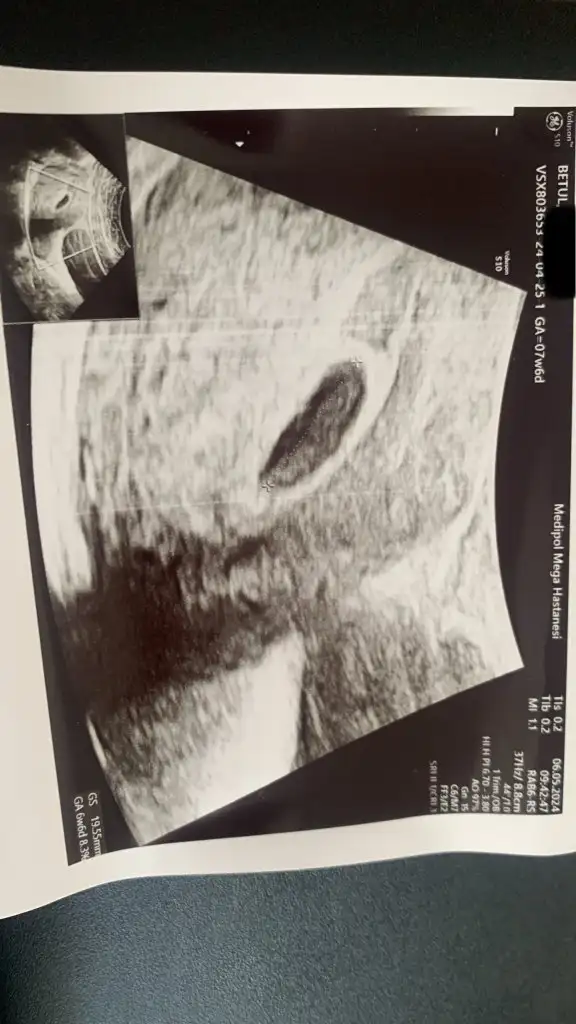

6+6 da kontrole gittim kese 25 mm olmuş. Hcg değerim de 37.000 olmuş. Ama bebek ve kalp atışı yok. Ultrasonda kese fotoğraftaki gibi gorunuyor.

Kesede ufak bir şey gorunuyor ama doktor bişey demedi. Haftaya tekrar bakacağız dedi. Sizce burada bir şey var mı? Benimle benzer durumu yaşayıp bebeği sonra gören var mı? Boş gebelik olmasından dolayı endişe duydum. Hcg değerlerim normal mi?

Yok canm su an 3 aylik olcam neredeyse hala kanamam yok bebegin boyu 4mm kaldi kalp atisida yok. Kese boyu 26mmBende aynı durumdayım siz kanama yaşamışmıydınız